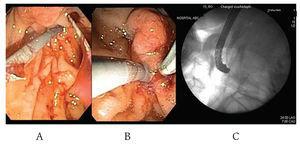

Once the wire was into the duodenal lumen several loops were formed (Figure 3) in order to avoid loosing access at the time endoscope exchange during the rendezvous procedure that was performed as previously described. (Figure 4 A-C). Using a duodenoscope (TJF-160F, Olympus) we observed that the bile duct drained from an independent and different orifice than the pancreatic duct within the ampulla. Access and drainage of the bile duct was performed sliding the duodenoscope over the guide wire; during the procedure, self-limited blood oozing occurred after biliary sphincterotomy. The patient underwent surgery next day and was discharged in good conditions.

Figure 4. Endoscopic view of the papilla of Vater showing a guide wire coming out thru the papliary orifice (A). A 7cm 10F plastic biliary stent is being advanced over the guide wire (B). Fluoroscopic view showing a standard duodenoscope used to palce the plastic biliary stent. (C) The duodenoscope was exchanged after inserting the guide wire into de common bile duct under endosonographic guidance.